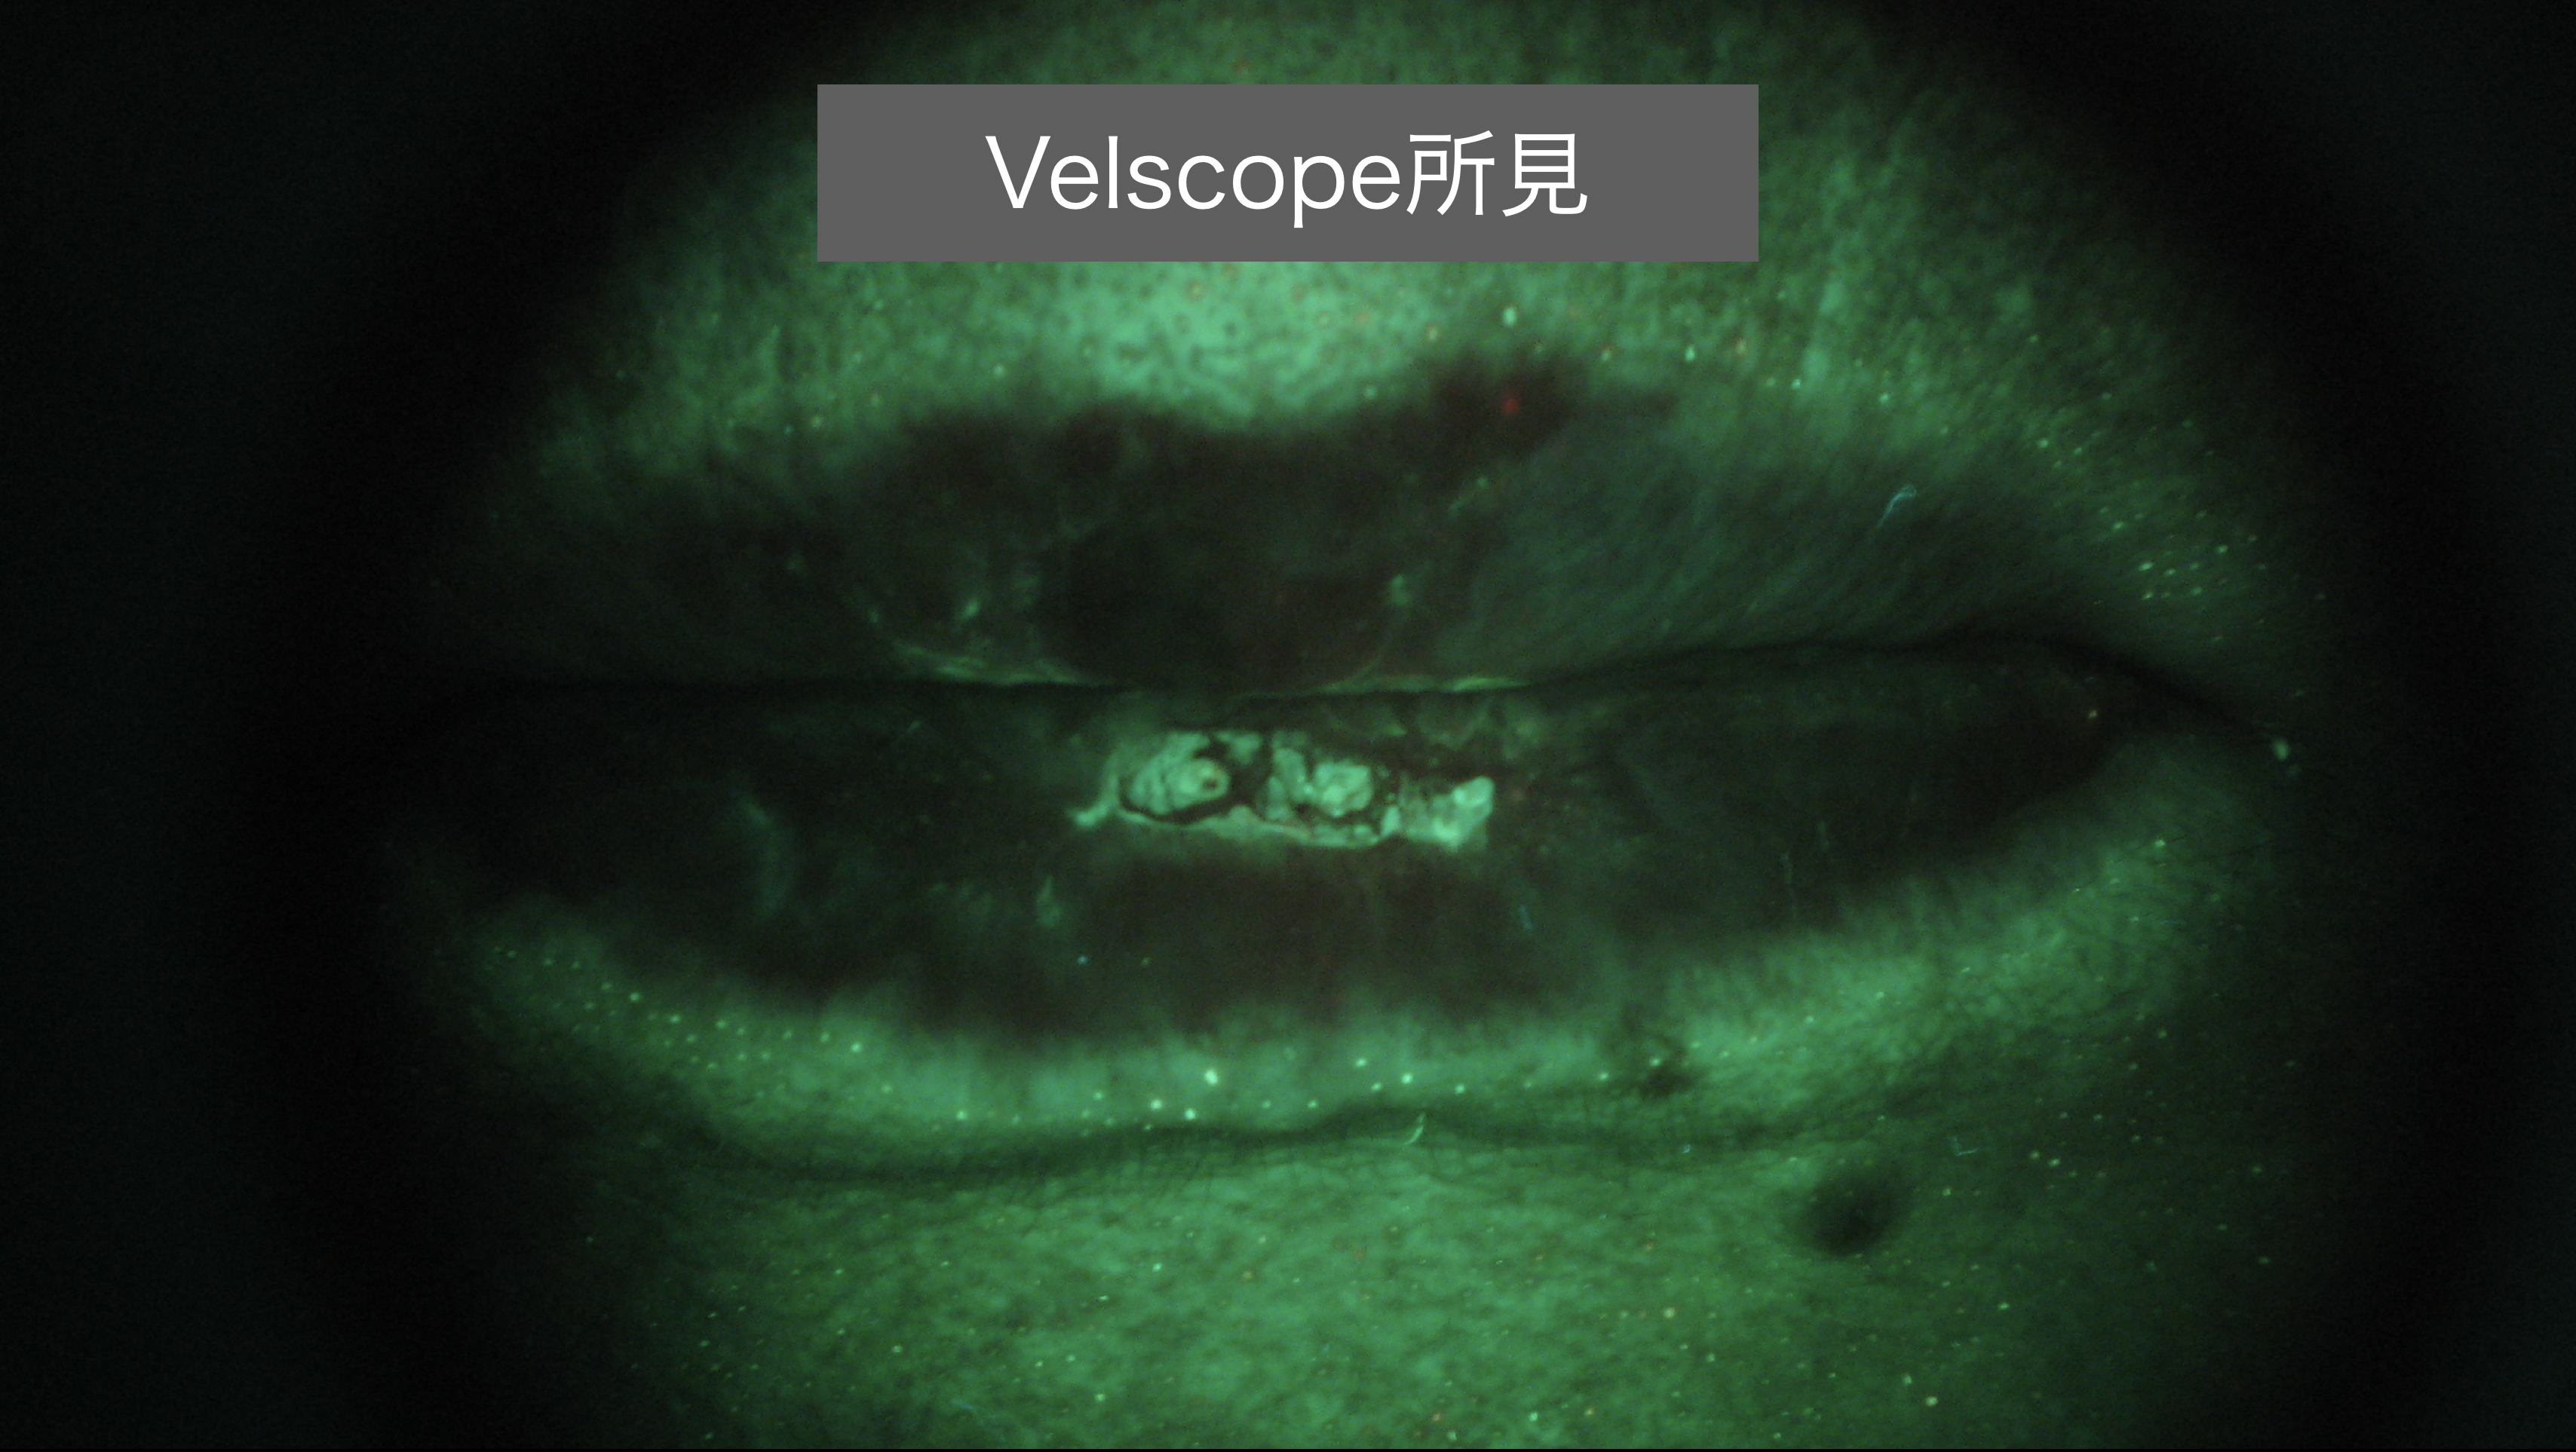

当院ではこれまでに特殊な光線を当てて性状変化を発見する機器(Velscope)も使用し、早期の発見に努めてきました。しかし、あくまで肉眼観察なので、本来、顕微鏡での確認を要する細胞レベルの細かな情報を得ることはできません。

当院ではこれまでに特殊な光線を当てて性状変化を発見する機器(Velscope)も使用し、早期の発見に努めてきました。しかし、あくまで肉眼観察なので、本来、顕微鏡での確認を要する細胞レベルの細かな情報を得ることはできません。